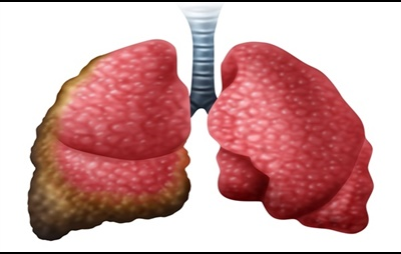

혈전은 반드시 폐암이 아니어도 나타날 수 있습니다 . 혈담이란 기침 후에 피가 나오 거나 가래에 피가 섞여 있는 것을 혈담 이라고 합니다 . 그러나, 의심스러운 폐암의 초기 증상의 혈담은, 선홍색의 비교적 선명한 피가 나오는 것을 의심해 봐야 합니다 . 이것은 암세포 때문에 폐가 괴사하기 때문 입니다 . 이 경우 폐암 초기보다는 암세포가 확장되었다고 보는 것이 좋습니다 . 폐암 환자의 25% 가 혈담을 했다고 통계가 나온 적이 있습니다 .